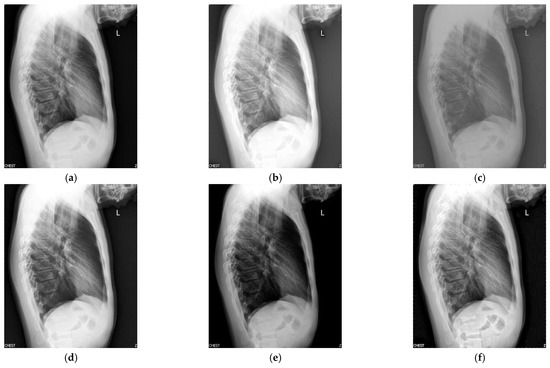

Figure 4 shows the enhancement images of eight approaches experimented on X-ray image 4. Figure 4a shows the original X-ray image 4; Figure 4b is the result computed by McCann—the image is too bright; Figure 4c depicts the image enhanced by RLBHE—the image is too dark; Figure 4d is the result achieved by RESIHE—the effect of enhancement is not obvious; the image obtained by TBCSSR is shown in Figure 4e—the image is dark; Figure 4f is the result enhanced by GDGIF—the details of the image are well preserved; Figure 4g and Figure 4h are the results enhanced by SMIPC and FuzzyII, respectively; Figure 4i is the result calculated by our approach. Table 4 shows evaluation data in Figure 4, and we can notice that the values of AG, H, ALC, SF and MG are the best.

Figure 4.

Comparison on X-ray image 4. (a) Original image; (b) McCann; (c) RLBHE; (d) RESIHE; (e) TBCSSR; (f) GDGIF; (g) SMIPC; (h) FuzzyII; (i) Proposed method.

Table 4.

The metric data of eight methods on X-ray image 4.